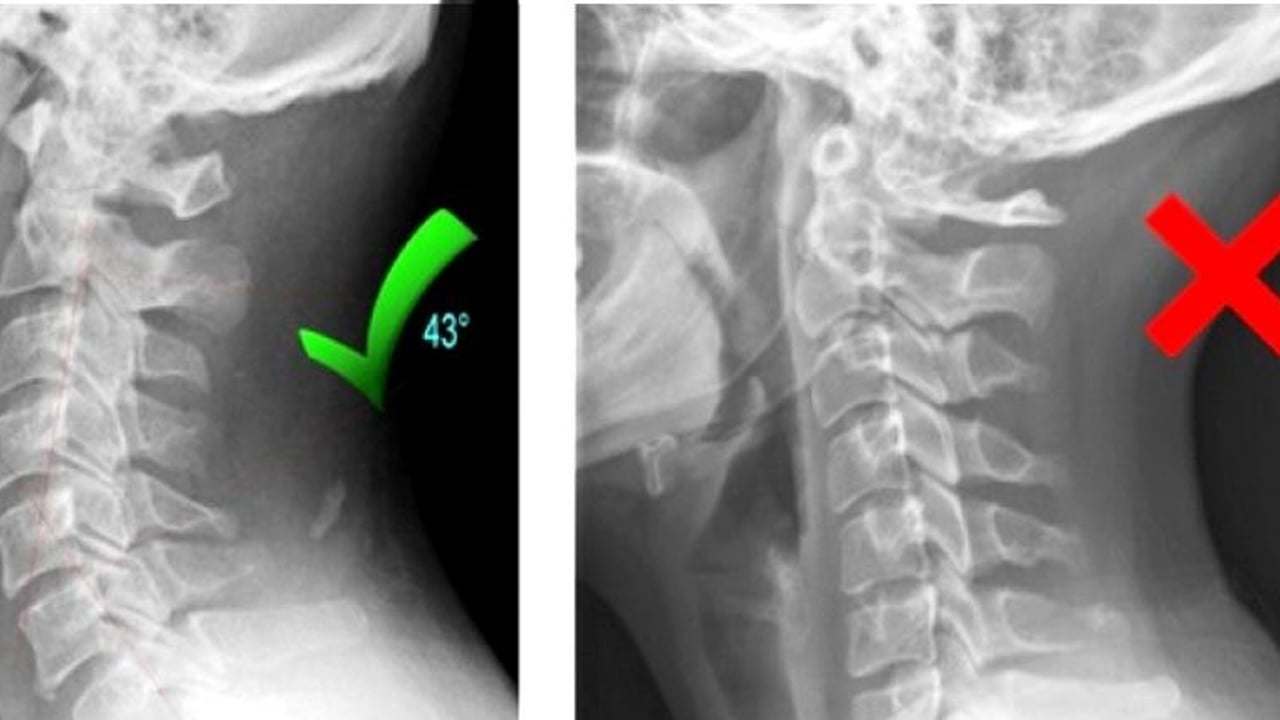

Boyun sağlığında uzun süreli yanlış duruşun boyun düzleşmesine neden olduğunu araştırmanın sonuçları ortaya çıktı! Tıpta adını servikal lordoz düzleşmesi olarak bildiğimiz bu sorun için adeta tamamen müdahale eden 7 tedavi seçeneği olabileceğini iddia edildi. İşte boyun düzleşmesi nasıl geçer?

Boyun Düzleşmesi Nedir? Boyun düzleşmesi kaba tabiriyle, boynun doğal kıvrımının azalıp düzleşmesidir. Tıpta servikal lordoz düzleşmesi olarak geçer. Omurga yapısı gereği boyun ve bel bölgesinde lordoz yani içe doğru çıkıntı gösterirken, sırt ve kuyruk sokumu bölgesi kifoz yani dışa doğru çıkıntı halindedir. Yanlış duruş, masa başında uzun çalışmalar, travma vb. sebeplerle boyun bölgesindeki içe doğru kıvrımlığın azalıp, düzleşme göstermesi de boyun düzleşmesi olarak isimlendirilir.

Boyun Düzleşmesi Belirtileri Nelerdir? Omurgamız olması gerektiğinden farklı bir şekle kıvrıldığında doğal olarak çevresindeki kasları ve diğer yapıları da farklı yönlere doğru çekerek spazm ve ağrıya sebep olur. Kişiden kişiye ve altta yatan sebeplere göre değişebileceği gibi ağrı omuzlara ya da tüm omurgaya yayılabilmektedir. Sinileri de sıkıştırabileceği için uyuşma ve karıncalanmaya, elektrik çarpar gibi giren ağrıya, baş ağrısı ve mide bulantısına sebep olabilmektedir. Boynunuzdaki kıvrımın azaldığı, daha düşük çene ve başın öne doğru duruşu da belirtilerin arasında yer almaktadır. Fakat düşük derecelerde bunu kendimiz fark edemeyebiliriz. Mutlaka bir fizik tedavi hekimine gidip görüntüleme teknikleri yardımıyla teşhis edilmesi gerekmektedir. Nedenleri Nelerdir? Boyun düzleşmesinin en yaygın nedeni duruş bozukluğudur. Boyun düzleşmesi nedenleri olarak; Uyku halinde ya da gün içerisinde yanlış duruş pozisyonları boyun düzleşmesine sebep olabilmektedir. Sürekli masa başında baş eğik şekilde çalışmak, hareketsizlik, boynu desteklemeyen yastık seçimi gibi sebeplerden olduğu gibi altta yatan başka sebeplerde olabilmektedir. Yaşlanmayla birlikte omurgada meydana gelene dejeneratif süreçler, spor aktiviteleri, kaza vb. sebeplerle ortaya çıkan travmalar, konjenital yani doğuştan gelen ya da doğum sırasında meydana gelen sebepler, bu bölgede meydana gelen tümör veya enfeksiyon yüzünden boyuna yapılan baskı ya da şişlikler de boyun düzleşmesine sebep olabilmektedir. Boyun Düzleşmesi Tedavisi! Belirtilerinden zaten bahsetmiştik. Bu belirtileri kendinizde fark edip fizik tedavi hekimine gittikten sonraki süreçten bahsedelim biraz… Öncelikle doktorunuz sizin tıbbi geçmişinizi ve fiziksel kontrolünüzü yaptıktan sonra röntgen, mr, tomografi gibi çeşitli görüntüleme tetkikleri isteyerek size tanıyı koyacaktır.